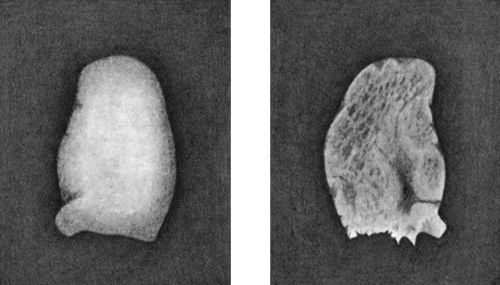

Fig. 1.—Ulcer of back of Hand covered by flap of skin raised from anterior abdominal wall. The lateral edges of the flap are divided after the graft has adhered.

| 1. | Ulcer of Back of Hand grafted from Abdominal Wall | 15 |

Another modification is to raise the flap but leave it connected at both ends like the piers of a bridge; this method is well suited to defects of skin on the dorsum of the fingers, hand and forearm, the bridge of skin is raised from the abdominal wall and the hand is passed beneath it and securely fixed in position; after an interval of 14 to 21 days, when the flap is assured of its blood supply, the piers of the bridge are divided (Fig. 1). With undermining it is usually easy to bring the edges of the gap in the abdominal wall together, even in children; the skin flap on the dorsum of the hand appears rather thick and prominent—almost like the pad of a boxing-glove—for some time, but the restoration of function in the capacity to flex the fingers is gratifying in the extreme.

Fig. 1.—Ulcer of back of Hand covered by flap of skin raised from anterior abdominal wall. The lateral edges of the flap are divided after the graft has adhered.